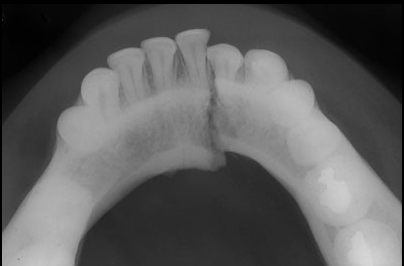

Paciente de 32 años acude a la consulta radiológica post accidente automovilístico por presentar múltiples contusiones. Al examen extraoral el paciente refiere dolor a la palpación de la región mentoniana, asi como de la zona geniana del lado izquierdo, presentando limitación a la apertura. En la radiografía panorámica (fig.1) podemos observar un trazo de fractura de forma vertical localizada en la sinfisis mentoniana que va desde el reborde alveolar hasta la basal mandibular, ademas de una linea radiolúcida de forma oblicua localizada a nivel subcondilar del lado izquierdo. En la radiografía posteroanterior tipo Towne (fig.2) nótese un desplazamiento hacia medial del cóndilo mandibular del lado izquierdo, y en la radiografía oclusal (fig.3) confirmamos el trazo de fractura en la sinfisis mentoniana con desplazamiento de segmentos.